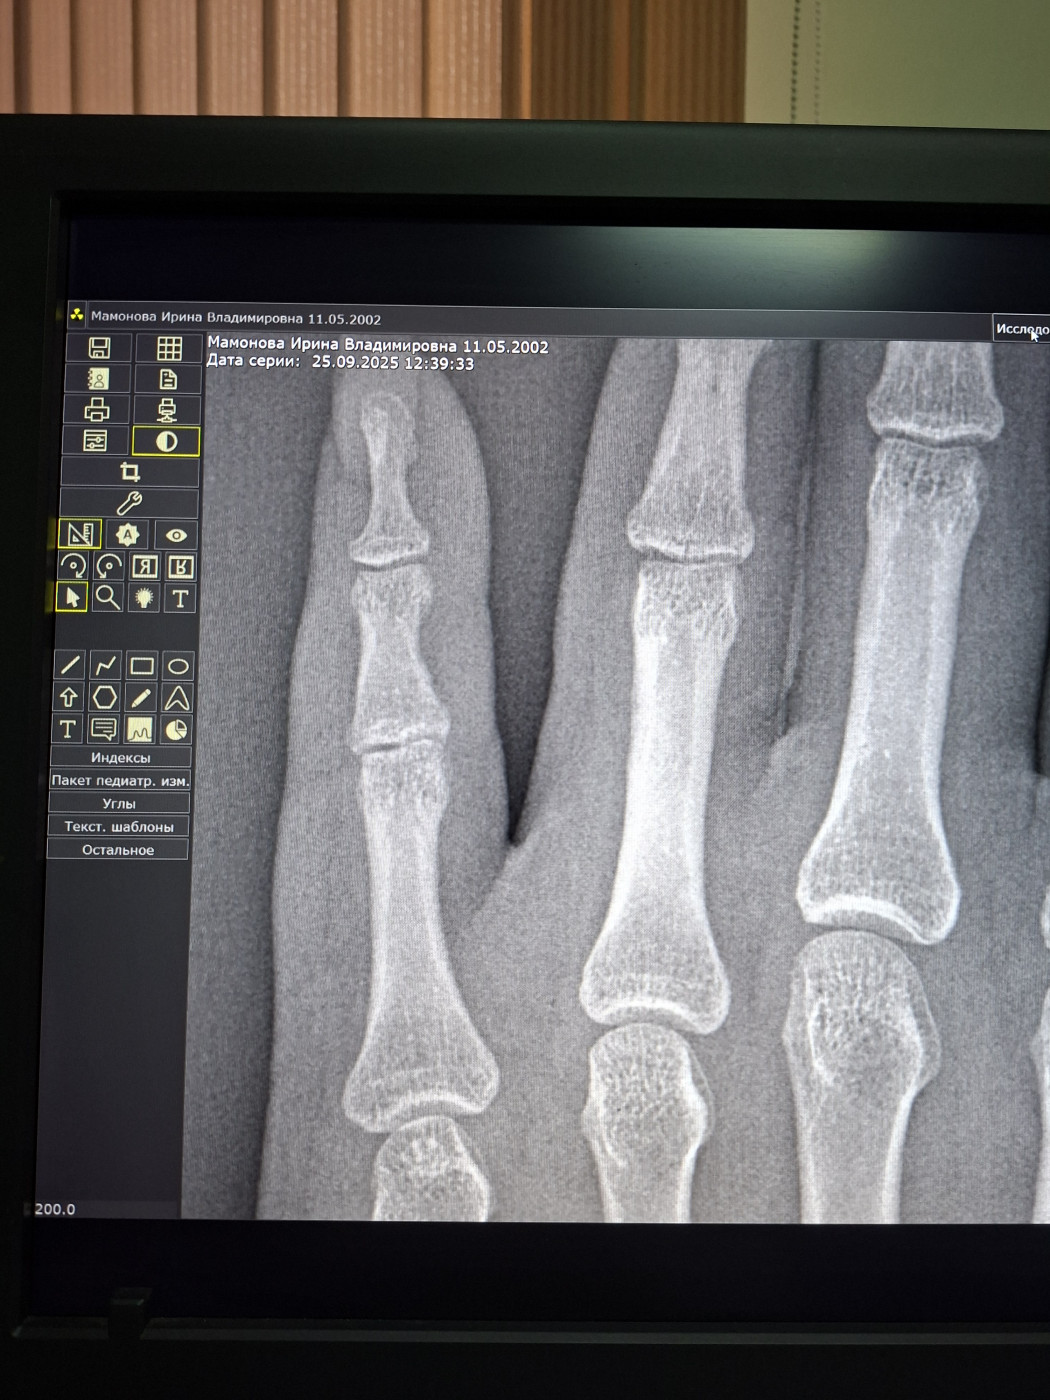

После падения, в гололед, перелом среднего пальца, на левой руке. Гипс …

Вчера пришемила в алюминевую дверь